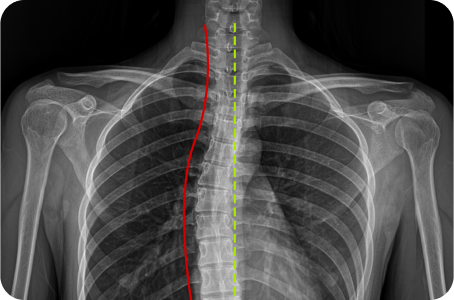

척추측만증

3차원 척추교정이란?

척추의 틀어진 방향과 휘어진 각도는 사람마다 모두 다릅니다.

옆, 앞, 뒤가 각자 틀어지고 꼬인 척추의 변형은 각도와 방향 모두를 고려한

3차원 척추 교정으로 바로잡아야 합니다.

정면, 측면 시각에서 틀어진 방향

척추 만곡의 각도

척추뼈 마디의 회전 변형